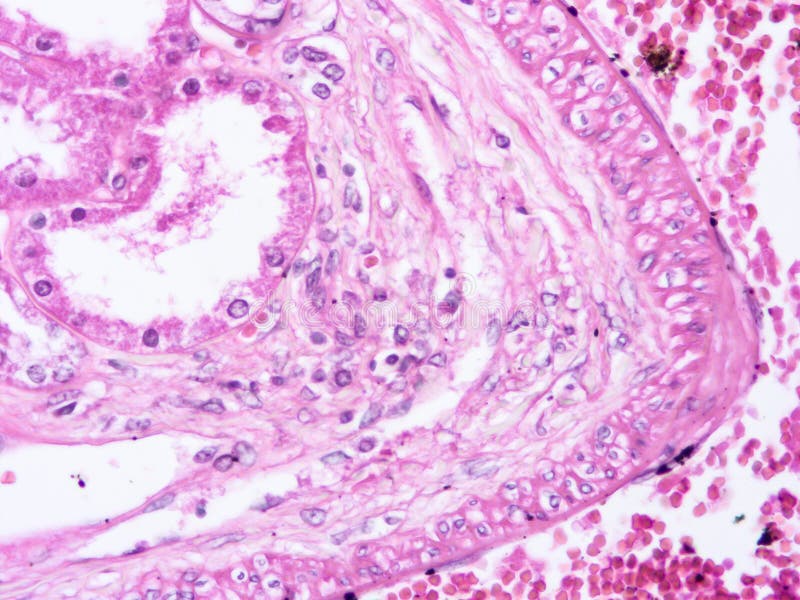

Histology of liver tissues a) Liver sections of healthy control group... Download Scientific

Histopathological images of liver tissue sections. a Normal liver... Download Scientific Diagram Liver Tissue Histology The liver is the largest solid organ and is located in the right upper quadrant of the abdomen. The hepatocytes are the main functional cells of the liver. They are large and polygonal epithelial cells that constitute roughly. Sheets of connective tissue divide the liver into thousands of small units called lobules. Parenchyma, which is represented by hepatocytes; Individual chapters. Liver Tissue Histology.